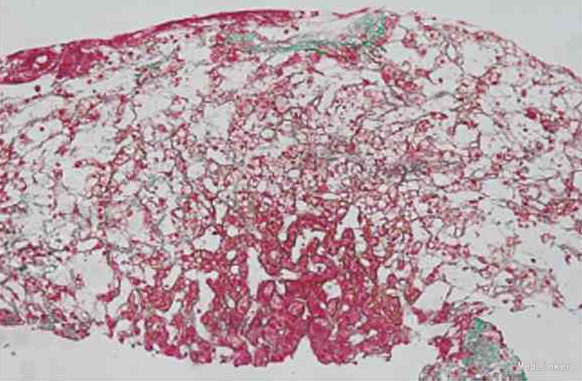

随访:未完成 讨论:该患者的血管彩超检查提示肝静脉纤细,血流减慢,但未见肝静脉或肝段下腔静脉狭窄、血栓,符合肝窦阻塞综合征的表现。 病理学检查提示肝组织淤血,肝窦高度扩张,尤其发现终末肝静脉内膜纤维性增厚、管腔狭窄,符合肝窦阻塞综合征的病理学特有表现。腹部CT检查提示3支肝静脉不显影,符合肝窦阻塞综合征的表现。 因此,结合血管超声检查、肝穿病理学检查及腹部增强CT检查结果,可排除巴德-基亚里综合征,确诊为肝窦阻塞综合征。 但肝窦阻塞综合征的常见病因是摄入吡咯双烷类生物碱(多存在于土三七中)或因器官移植后发生免疫排斥所致,这与该患者不符。 但是,该患者在6年前曾经接触过高浓度的二氧化硫,时间为半年,考虑其肝窦阻塞综合征的病因可能与此相关。因此,该患者的最终诊断为肝窦阻塞综合征。